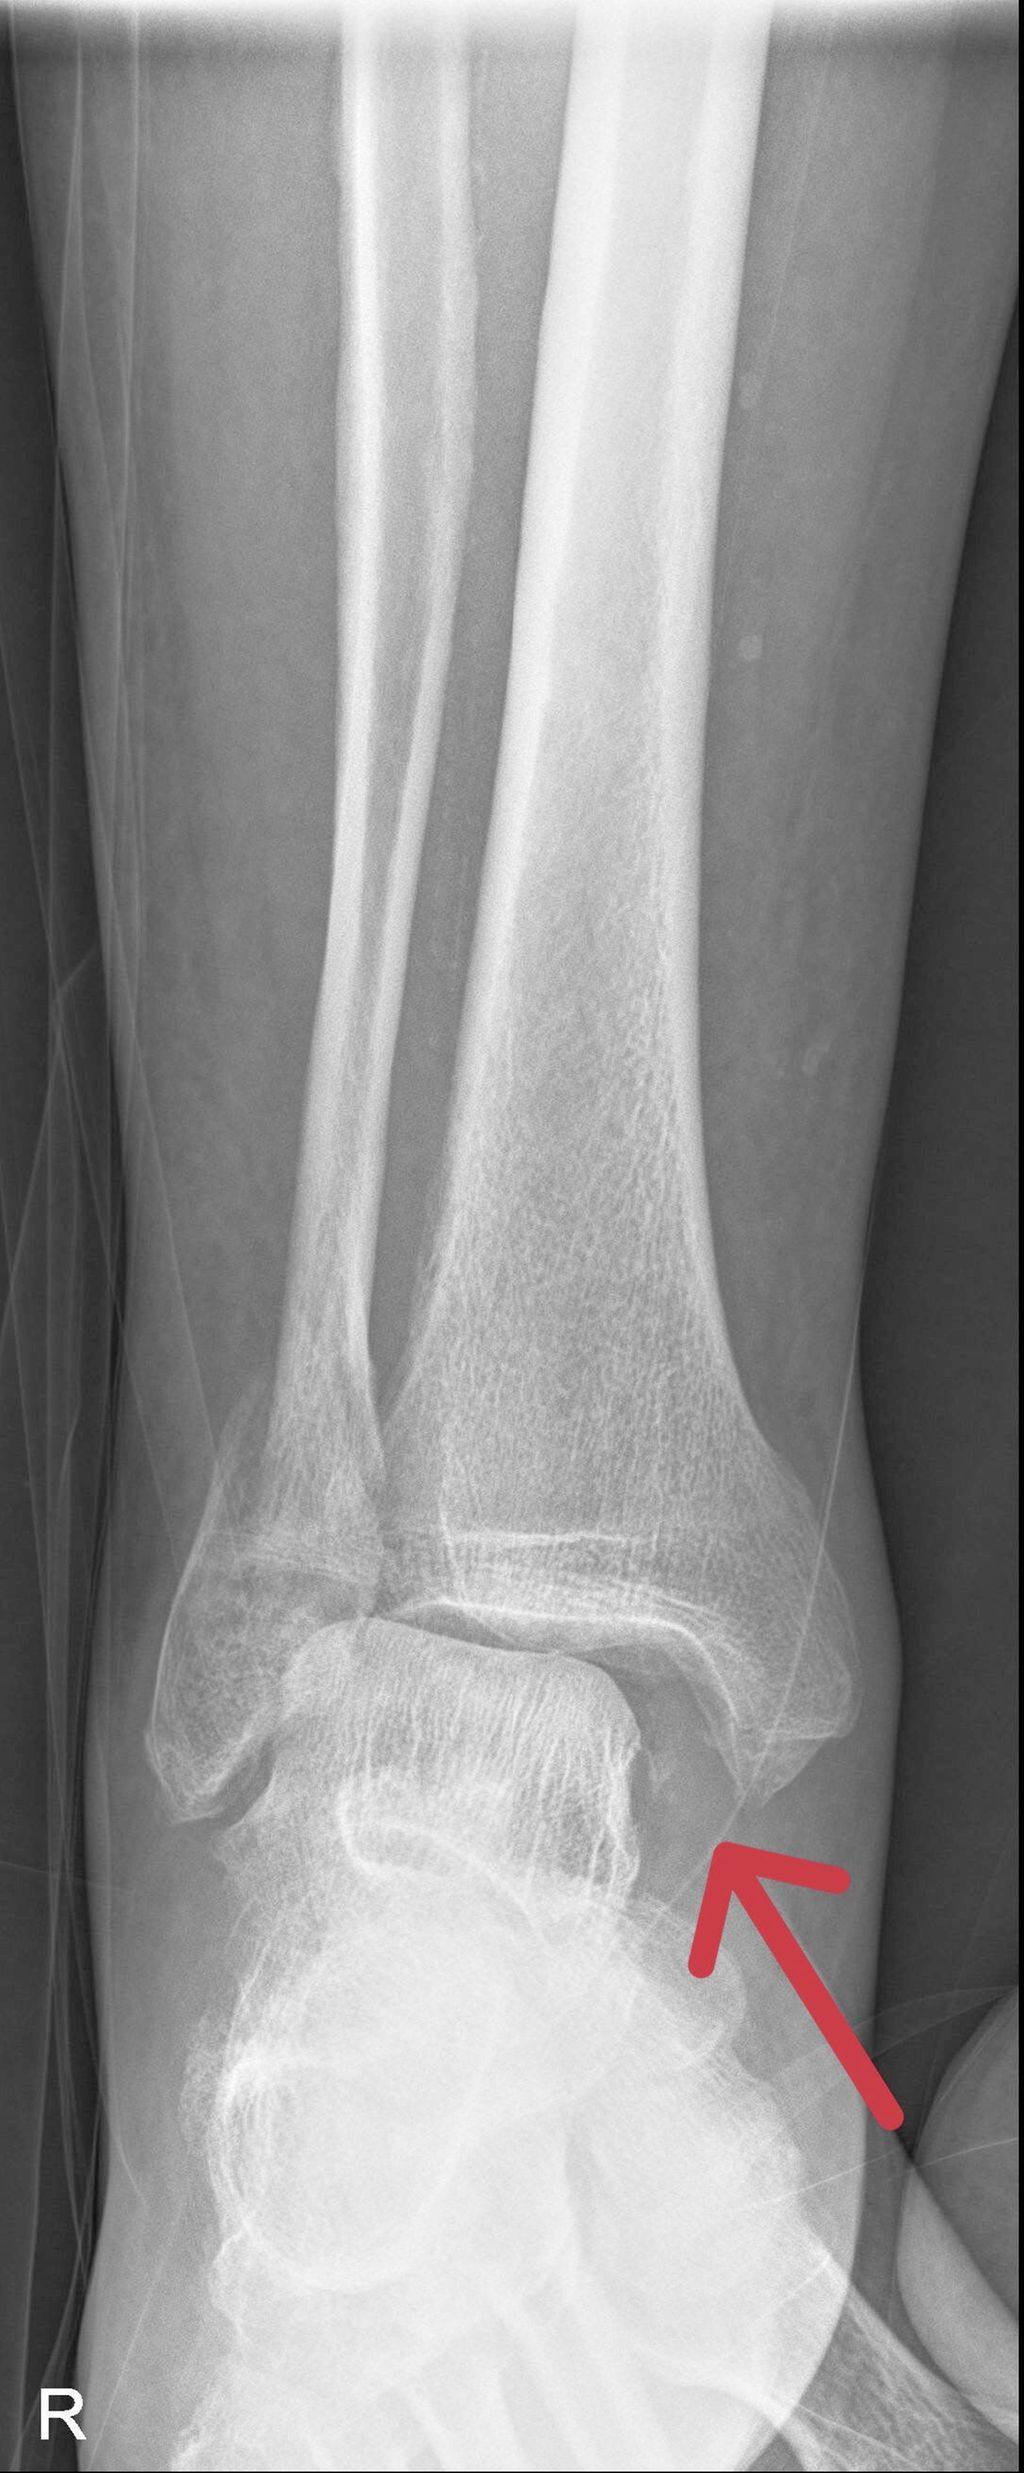

Als Standarddiagnostik erfolgt eine Röntgenaufnahme des Sprunggelenkes in zwei Ebenen. Die a.p-Aufnahme wird in 15–20° Innenrotation des Unterschenkels (Mortise-View) durchgeführt. Zur Beurteilung der Integrität des Deltabandes ist der Abstand zwischen Sprungbein und der lateralen Kortikalis des Innenknöchels („medial clear space“, MCS), entscheidend. Bei Werten <4mm ist das Deltaband intakt und die Fraktur stabil. Ist der MCS größer als 4mm oder gibt es klinische Zeichen einer Deltabandverletzung, muss weitere Diagnostik zur Feststellung der Stabilität durchgeführt werden.

Eine weitere Möglichkeit ist die Röntgenaufnahme im Stehen unter Vollbelastung nach 5–10 Tagen. Zeigt sich hierbei ein unauffälliger MCS, werden in der Literatur gute klinische Ergebnisse bei konservativer Behandlung beschrieben. Dawe et. al stellten fest, dass der „Gravity-Stresstest“ bei Außenknöchelfrakturen signifikant häufiger positiv ausfällt als der Röntgenbelastungstest (45% vs. 3,7%). Dementsprechend höher war die Anzahl der operierten Patienten und der damit verbundenen Komplikationen. In der Studie von Holmes et. al wurden bei 51 Patienten mit einem MCS <7mm (∅ 4,42mm) im „Gravity-Stresstest“ normale Werte in der Röntgenuntersuchung in Vollbelastung beobachtet. Diese Patienten wurden konservativ behandelt und zeigten gute klinische und radiologische Resultate. 90–98% der isolierten Außenknöchelfrakturen können trotz positiver „Stresstests“ oder klinischer Zeichen einer Instabilität bei negativem Röntgenbelastungstest konservativ mit gutem Outcome behandelt werden.

Eine Dislokation der Außenknöchelfraktur scheint wenig Einfluss auf das funktionelle Outcome zu haben. Es hat sich gezeigt, dass stabile Frakturen bis zu einer Verschiebung von 5mm konservativ mit gutem Outcome versorgt werden können.